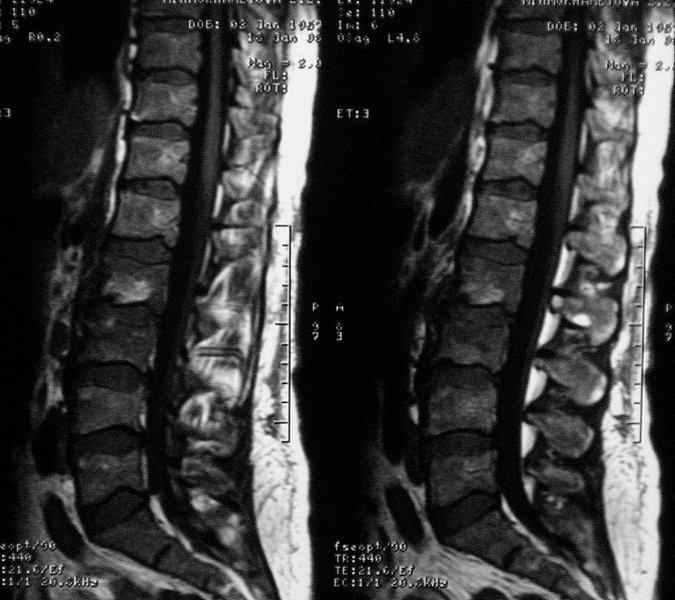

Отправляю MRI в динамике, снятые с пленки на фотоаппарат.

|

MRI через три недели

По данным представленных КТ и МРТ у больной имеется достаточно выраженная степень деструкции тел позвонков (около 30% общей костной массы тела позвонка), что определяет высокий риск возникновения патогических переломов и появления локальной кифотической деформации на этом уровне.

Уважаемый доктор! судя по последнему МРТ процесс затрагивает соседние позвонки с переходом процесса через диск. Для туберкулёза как раз и характерна картинка "целующихся" позвонков. При бактериальном процессе диск страдает лишь вторично. Туберкулиновые пробы могут быть в пределах нормы, лёгкие - чистые. Вообще туберкулёз последнее время стал очень коварен и атипичен. Такие случаи отмечались у детей старшего возраста.